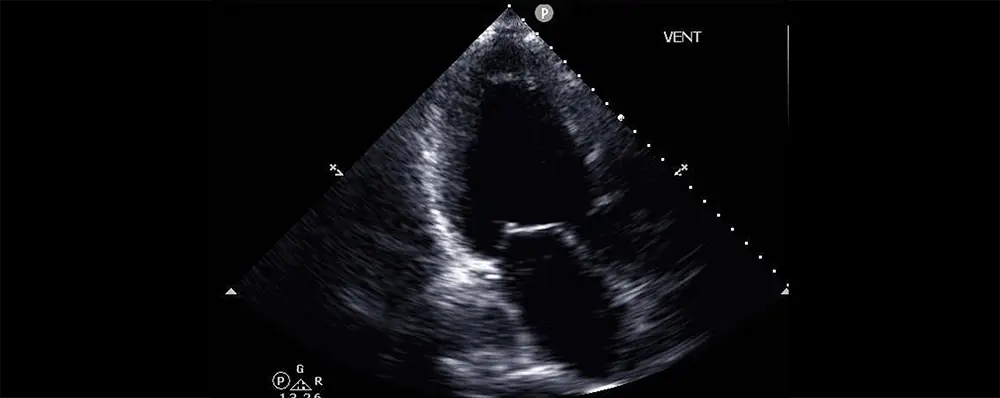

Applying artificial intelligence techniques to cardiac ultrasound data may make it easier to identify patients with advanced heart failure, according to a study led by investigators at Weill Cornell Medicine, Cornell Tech, Cornell Ann S. Bowers College of Computing and Information Science, Columbia University Vagelos College of Physicians and Surgeons and NewYork-Presbyterian. The findings offer the prospect of better care for many thousands of patients who may be overlooked due to the difficulty of diagnosing their condition.